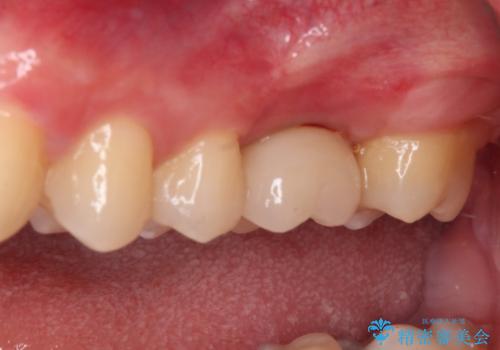

奥歯の虫歯は抜歯が必要であったので、矯正治療前に抜歯をし、矯正治療と並行してインプラントによる補綴治療を行うこととしました。

当院の特徴は、矯正治療とインプラント補綴治療の担当医が同じ歯科医師であるため、両方の治療を並行して行うことができます。